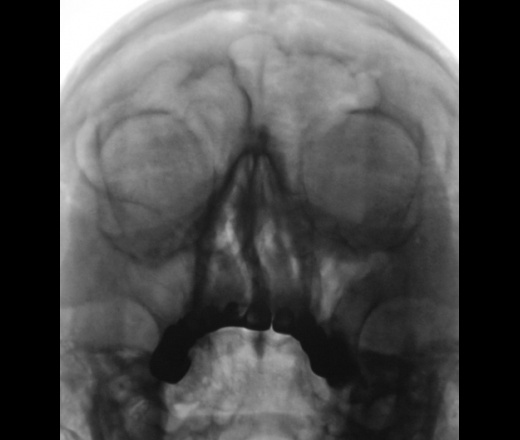

Думаю, что снижение пневматизации левой гайморовой пазухи обусловлено недостаточным её развитием, толстыми костными стенками пазухи.

Пристеночный отек слизистой...толщину стенок считаю нормальной.

У пациента, все дела начались после травмы (обратите внимание носовая перегородка искривлена).

А я выскажусь в защиту своей первоначальной версии. Выраженное утолщение наружной стенки пазухи, по плотности сопоставимо с плотностью рядом расположенной скуловой костью. Не может быть ограничен воспалительный процесс в пазухе только одной стенкой, следовательно на передней и задней стенках должно быть такое же утолщение слизистой или примерно такое же, а следовательно мы бы видели выраженное общее затенение пазухи, а на представденных Р-граммах прозрачность левой пазухи на мой взгляд даже больше, чем правой, где такого утолщения нет. Вывод - утолщена только наружная стенка и, моё мнение, именно за счёт костной стенки.

Коллега, простите, но изменения НА ВСЕХ стенках...и это очевидно.